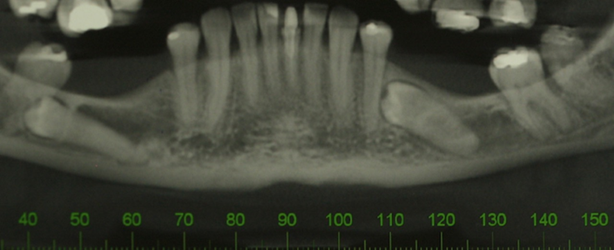

Case 1: a 37-year-old patient sought treatment with osseointegrated implants to replace a removable prosthesis in the posterior region of the mandible. In the imaging exams, a lower premolar was discovered included in the edentulous area (figure 1). After evaluation by an orthodontic specialist, traction was ruled out. In an evaluation using cone beam tomography, a close relationship was observed between the tooth and the inferior alveolar nerve from the crown to the apex, the nerve was embraced by the tooth (figure 2). When assessing the risk-benefit of tooth removal, the high chance of paresthesia was considered, in addition to a probable large height defect after tooth extraction.

Figure 1: Panoramic radiograph showing an impacted premolar in an edentulous area (third quadrant).

Figure 2: Cone beam computed tomography showing the proximity of the mandibular canal to the root apex of the impacted premolar.